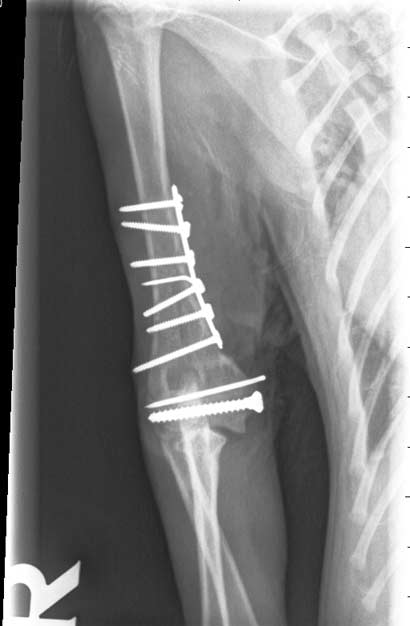

nach der OP

Noch an den Weihnachtstagen liessen wir Looping in eine chirurgische Klinik bringen, damit er schnellstmöglich operiert und seine Frakturen entsprechend versorgt werden konnten. Die Brüche sind wohl durch einen Sturz/Sprung von extremer Höhe entstanden, vielleicht durch den Sturz von einem Balkon?? (Leider haben immer noch viele Leute ungesicherte Balkone und unterschätzen die Neugierde und den natürlichen Jagdinstinkt von Katzen wenn z.B. ein Vogel vorbei fliegt)